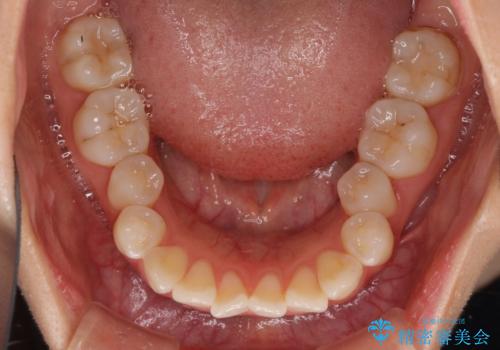

- 上下前歯のデコボコを気にして来院された患者様です。

インビザラインによる上下歯列の拡大と、IPR(歯と歯の間を削る)にるスペースの獲得により、前歯のデコボコを改善することとしました。

しっかりと装着時間を遵守してくださったので、思い通りの歯列に整えることができました。

結婚式前に終了させることができ、患者様には大変満足していただきました。